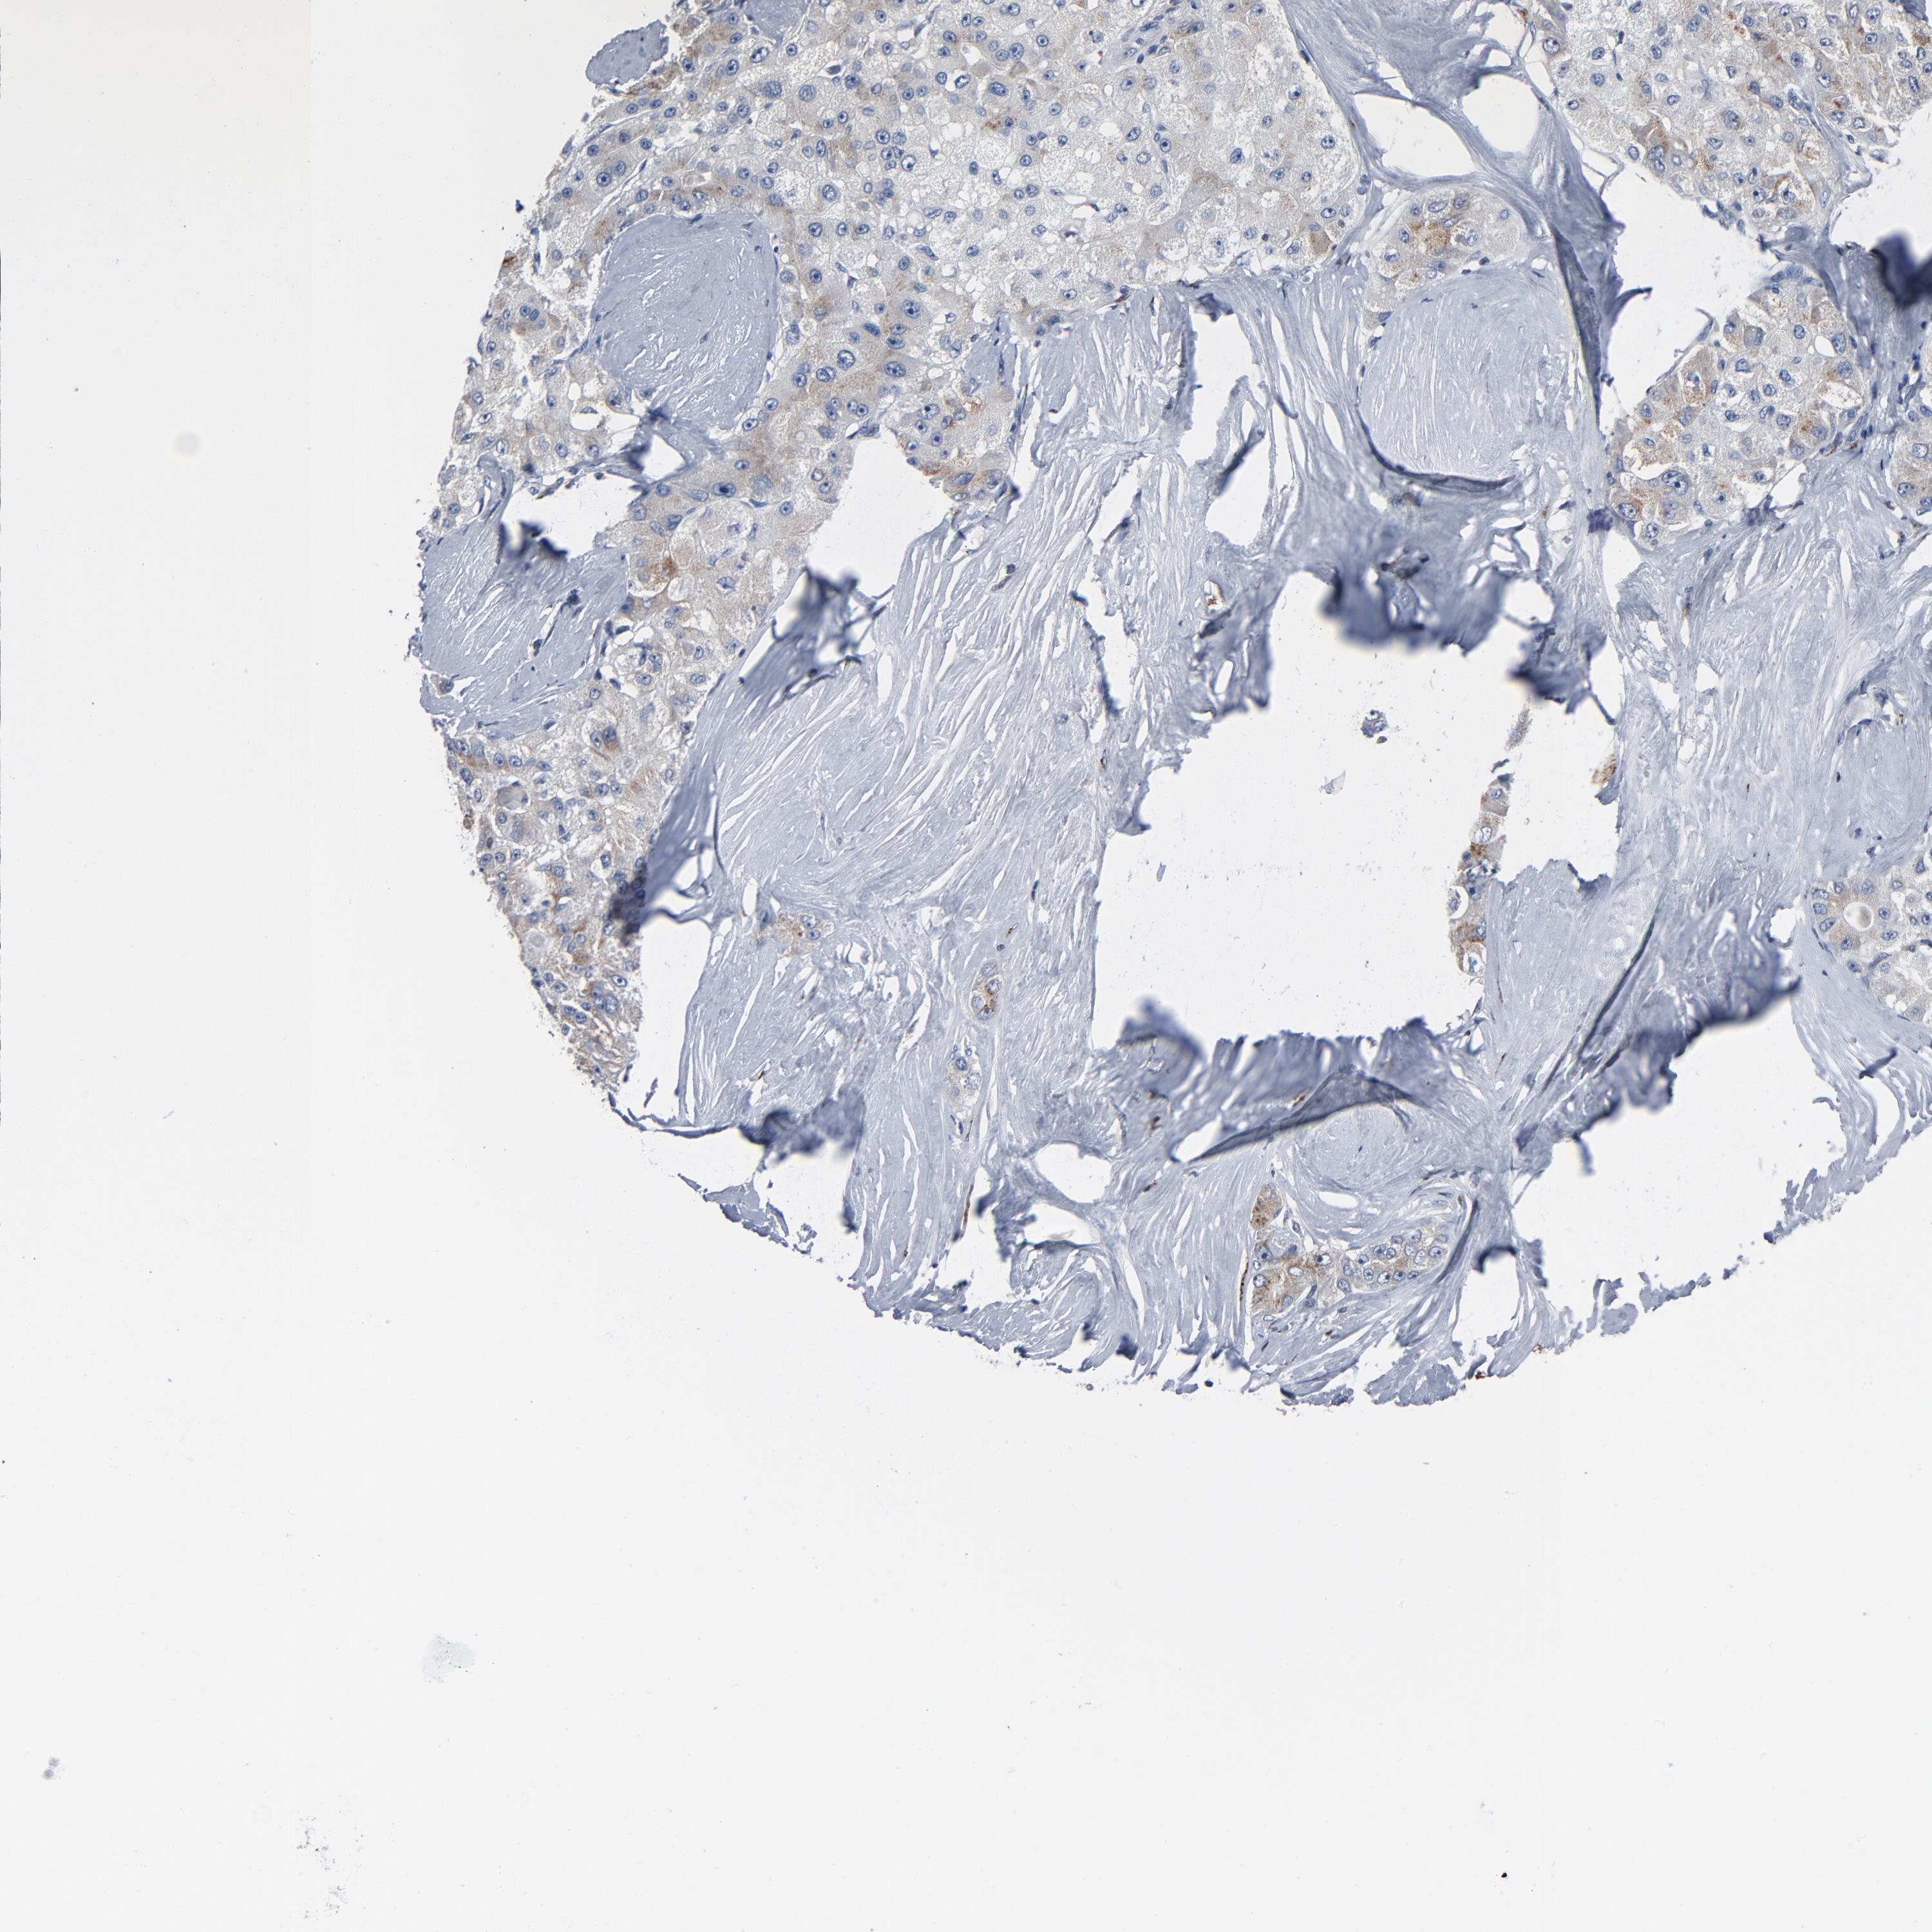

LIVER CANCER - Protein expressioni

A mouse-over function shows sample information and annotation data. Click on an image to view it in a full screen mode. Samples can be filtered based on level of antibody staining by selecting one or several of the following categories: high, medium, low and not detected. The assay and annotation is described here.

Note that samples used for immunohistochemistry by the Human Protein Atlas do not correspond to samples in the TCGA dataset.

Antibody stainingi

Antibody staining in the annotated cell types in the current human tissue is reported as not detected, low, medium, or high, based on conventional immunohistochemistry profiling in selected tissues. This score is based on the combination of the staining intensity and fraction of stained cells.

Each image is clickable and will lead to virtual microscopy that enables deeper exploration of all samples and also displays staining intensity scores, fraction scores and subcellular localization as well as patient and tissue information for each sample.

Antibody HPA003720

Staining

High

Medium

Low

Not detected

Intensity

Strong

Moderate

Weak

Negative

Quantity

>75%

75%-25%

<25%

None

Location

Nuclear

Cytoplasmic/membranous

Cytoplasmic/membranous,nuclear

Cholangiocarcinoma

Carcinoma, Hepatocellular, NOS